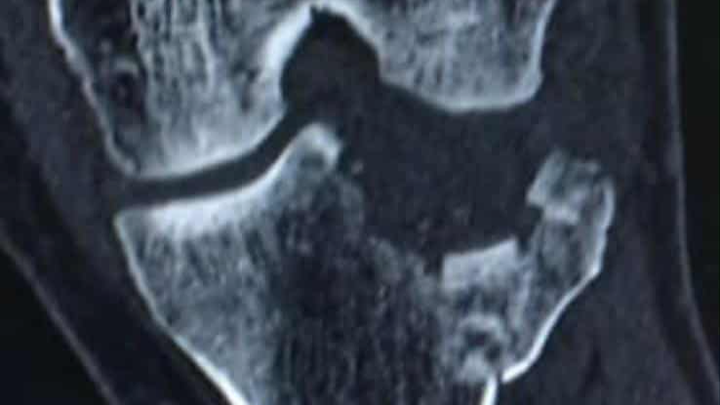

On September 15, 2024, I suffered a serious injury and broke my tibia. Since that day, my life has been turned upside down. I’ve been unable to work and do the things I normally take pride in—providing for myself and my family.

I’ve done my best to stay strong and push through this difficult time, but the reality is that recovery has been longer and more challenging than I ever expected. Now, I am facing surgery scheduled for April 23, and with it comes medical expenses that I am simply not able to handle on my own.